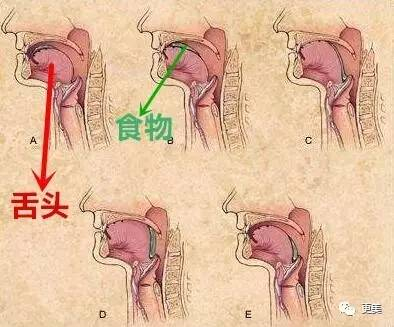

正确的呼吸是空气经由鼻腔到达气管,大概是这个路线

但许多人的呼吸习惯是经由口腔进入气管,舌头不再紧贴上颚,后果很明显

1。舌头位置向下压,口腔的空间就变大了,舌尖顶到牙齿,导致牙齿一直受到向外的力,慢慢形成牙凸

2。口腔空间变大,双下巴就形成了